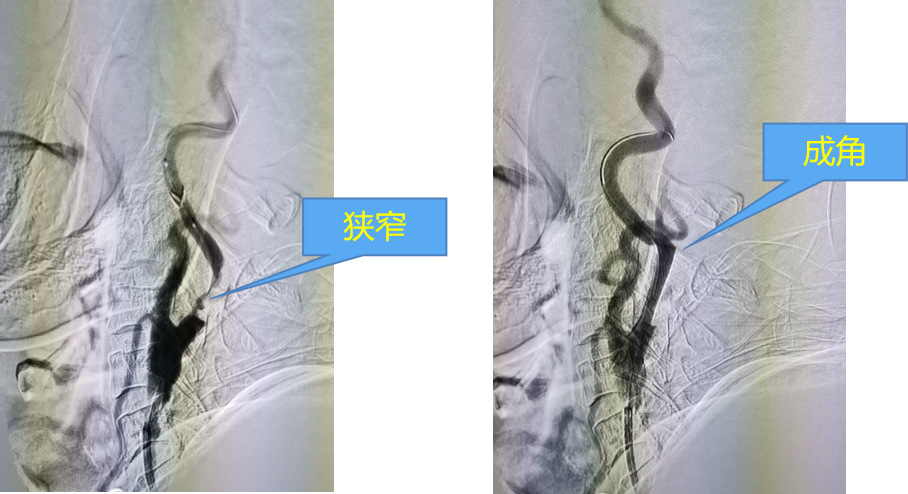

支架内血栓形成:与支架覆盖不足以及支架对斑块的挤压有关,而斑块破裂溢出形成血栓

支架网孔面积比较:开环支架、FREE CELL、Xact、BASE等不同支架的网孔面积比较。